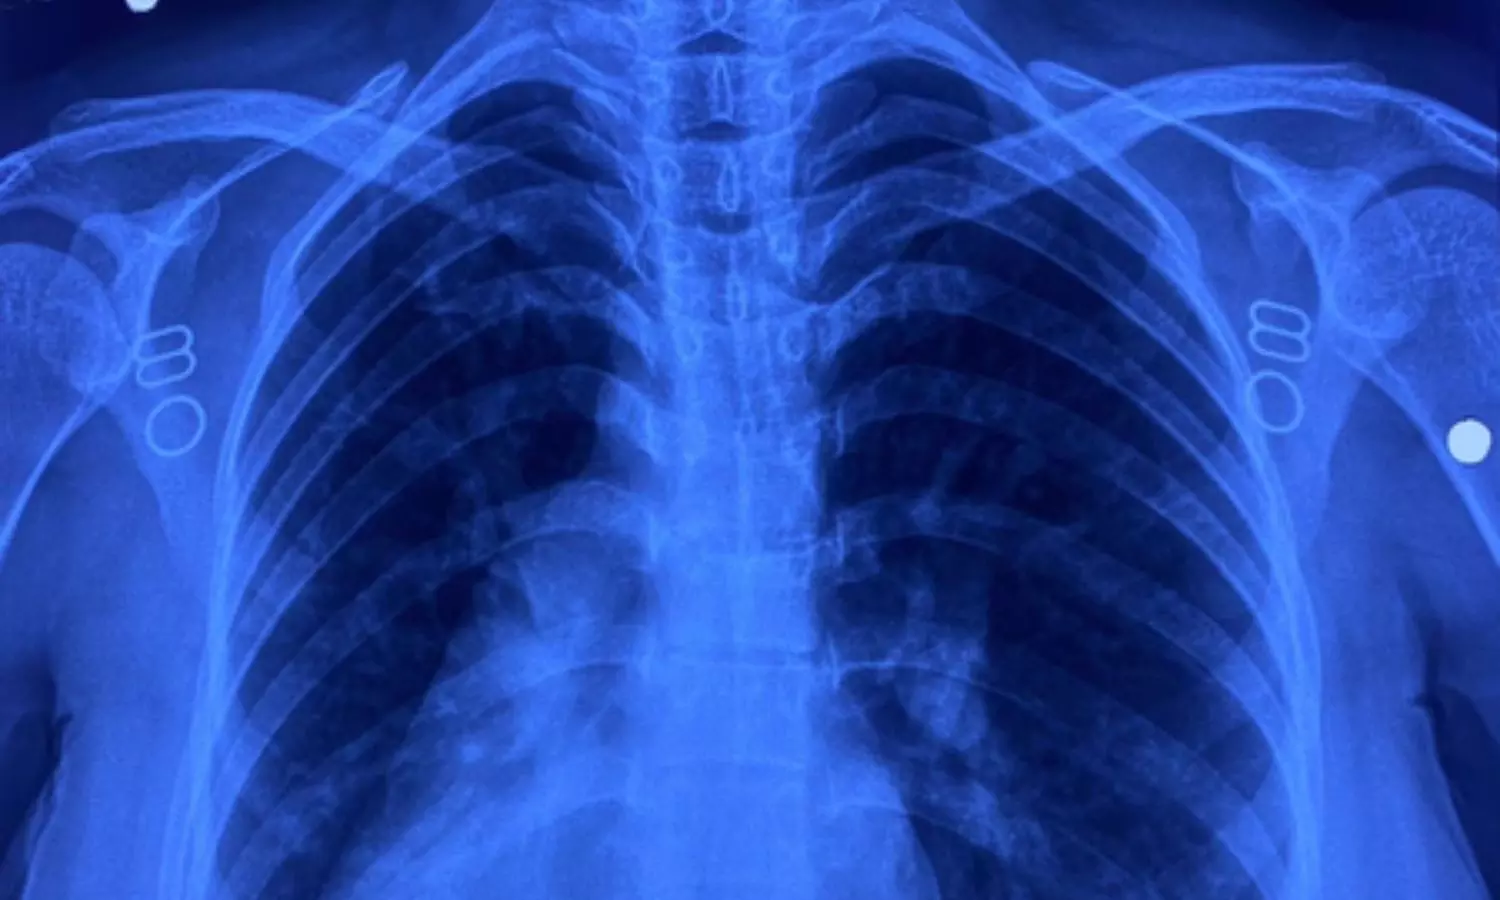

इस मरीज के सभी अंग सामान्य जगह के उलट यानी मिरर इमेज में थे। उसके दिल की जगह दाईं ओर थी, लिवर बाईं ओर, प्लीहा दाईं ओर और पेट भी दाईं ओर था। इसके साथ ही मरीज में जन्मजात आंशिक एट्रियोवेंट्रिकुलर कैनाल दोष जैसी जन्मजात हृदय रोग की समस्या भी थी।

इस सर्जरी में कई चुनौतियां थीं। सबसे बड़ी चुनौती यह थी कि जन्मजात हृदय दोष, वाल्व और संवेदनशील कंडक्शन सिस्टम के अत्यंत निकट था। इसके अतिरिक्त, रक्त वाहिकाओं की 'मिरर इमेज' (विपरीत दिशा) स्थिति ने सर्जरी को और भी पेचीदा बना दिया था। महज 4 सेंटीमीटर के छोटे चीरे के माध्यम से उपकरणों को संभालना और सूक्ष्म टांके लगाना तकनीकी रूप से बेहद कठिन कार्य था। मरीज को हृदय–फेफड़ों की मशीन के माध्यम से बायपास करना पड़ा, जिससे टीम की विशेषज्ञता और अनुभव की जरूरत थी।